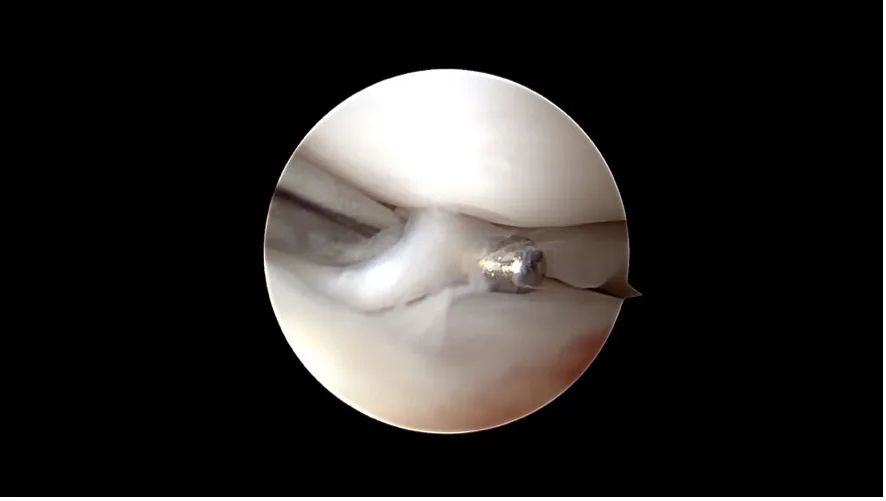

An incipient cruciate ligament tear is hidden beneath the remaining cruciate ligament, which appears unremarkable at first glance.

A complete cruciate ligament rupture